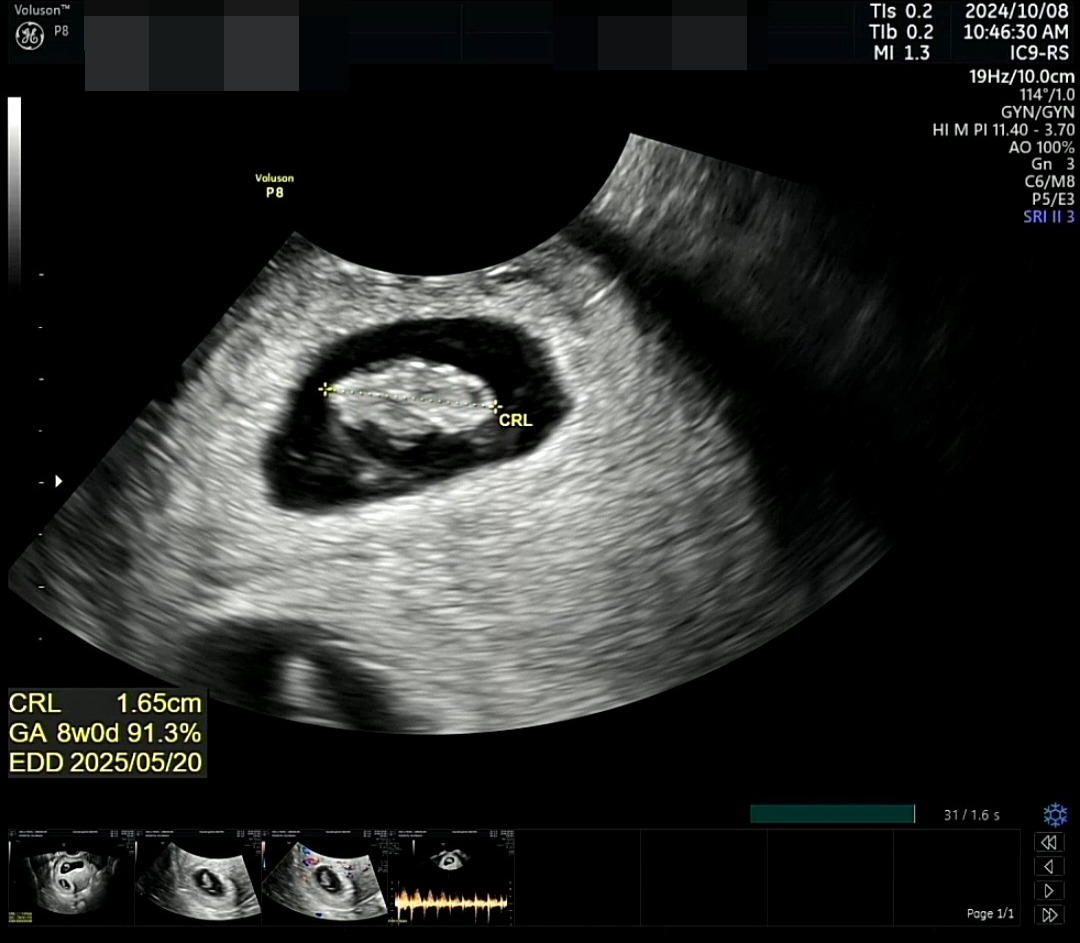

벌써 임신 8주 차, '임산부'라는 호칭에 이제 막 익숙해져 가고 초반엔 그저 '혼란'이었던 다양한 임신 증상들에 조금은 적응해갈 즈음..

함께 병원을 가는 것은 처음이라 뭔가 특별한 기념일이 된 것 같은 기분이 들었다. 남편도 함께 우리 요셈이를 분만까지 담당해 주실 의사 선생님을 만났고, 함께 초음파를 보며 그동안은 동영상으로만 보았던 요셈이의 쿵쿵 뛰는 심장소리를 직관하였다.

요셈이는 그새 또 자라 1.65cm가 되어 있었다. 이제 모양도 제법 생명체 같았다.

심장도 잘 뛴다고 하였다.